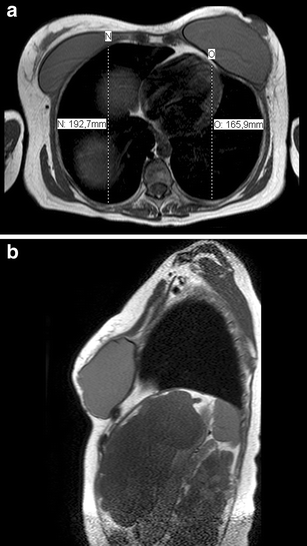

Transverse (a) and sagittal (b) magnetic resonance imaging slides taken directly after placement of bilateral permanent implants. Note displacement of the ribs and decreased anteroposterior diameter of the chest wall on the left side